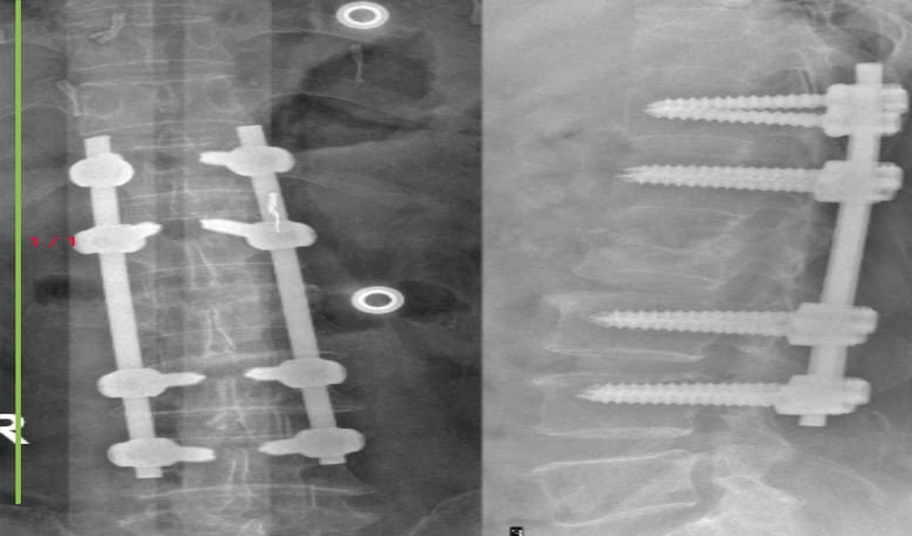

4.2.3. Điều trị ngoại khoa Chỉ định khi thoát vị đĩa đệm, trượt đốt sống gây đau thần kinh tọa kéo dài, hoặc có hẹp ống sống với các dấu hiệu thần kinh tiến triển nặng ảnh hưởng tới chất lượng cuộc sống mà các biện pháp điều trị nội khoa không kết quả. Trong trường hợp đĩa đệm thoái hóa nhiều, có thể xem xét thay đĩa đệm nhân tạo.

Điều trị Phục hồi chức năng kết hợp cho bệnh nhân tại Bệnh viện Đa Khoa Tỉnh Quảng TrịĐiều trị bằng Phương Pháp Y học cổ truyền: Xông hơi thuốc, điện châm, xoa bóp bấm huyệt…. tại bệnh viện Đa khoa Tỉnh Quảng TrịMRI của Bệnh nhân thoát vị đĩa đệm - hẹp ống sống, được điều trị bằng phương pháp

Phẫu thuật tại bệnh viện đa khoa tỉnh Quảng Trị